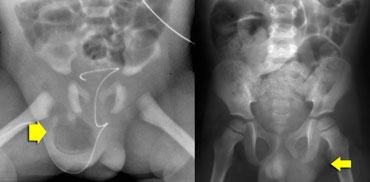

Hernia

LEFT: herniated bowel in preterm.RIGHT: left-sided hernia in constipated child due to intermitted herniation of sigmoid.

Thoát vị ở trẻ em rất phổ biến, đặc biệt ở trẻ sinh non.

Đôi khi chúng ta có thể nhìn thấy chúng trên phim chụp thường quy như trong trường hợp ở hình bên trái.

Nếu chúng chứa đầy quai ruột, chúng dễ dàng được phát hiện, nhưng đôi khi các thoát vị này chỉ chứa mô mềm

Khám siêu âm bắt đầu với trẻ ở tư thế nằm và sau đó tiếp tục ở tư thế đứng.

Ruột hoặc mạc nối có thể nhìn thấy tách biệt với tinh hoàn (hình).

Quai ruột đi xuống qua ống phúc tinh mạc chưa đóng.

Thoát vị nghẹt là nguyên nhân gây đau bìu cấp tính.

Nhu động ruột gợi ý khả năng sống còn và sự vắng mặt của nhu động ruột là dấu hiệu đáng lo ngại cho tình trạng nghẹt.